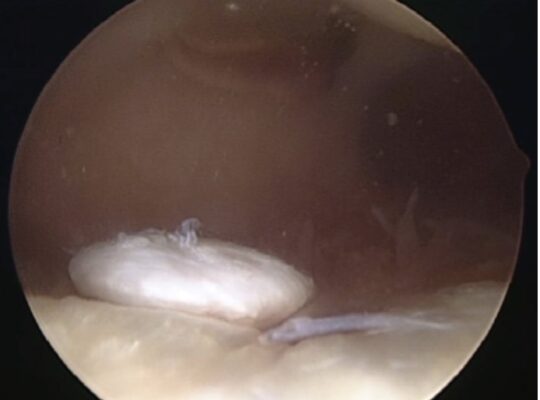

Bệnh nhân có thể biểu hiện tràn dịch, đau tại chỗ và có thể có các triệu chứng cơ học. Nếu một mảnh toàn bộ độ dày bị bong ra một phần hoặc toàn bộ, bệnh nhân có thể có cảm giác bị khóa hoặc “vật thể lỏng lẻo” khi mảnh đó di chuyển trong khớp gối (Hình 2). Nếu tổn thương lan đến xương dưới sụn, sẽ có tình trạng tụ máu khớp. Một số bệnh nhân có thể có các triệu chứng mơ hồ hơn mà không có tràn dịch rõ và đau lan toả hơn, khiến khó chẩn đoán rõ ràng.

- Vi gãy xương (MF) liên quan đến việc cắt bỏ phần sụn bị tổn thương bằng nội soi thành các cạnh vuông ổn định. Vùng sụn vôi hóa được lấy bỏ và tiến hành xuyên thủng vỏ bằng dùi, cho phép chảy máu tủy và hình thành cục máu đông (Hình 3).